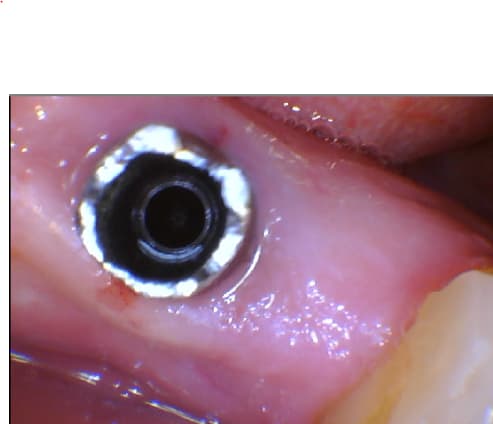

Merci fran pour l'info mais justement , j'ai vu la patient jeudi avec sa couronne déscellée, j'ai dévissé sans problème après avoir enlevé le ciment qui allait jusqu'à la vis mais impossible de sortir le pilier .

Il y a même encore des traces de ciment là où la vis appuyait dans le pilier .

J'ai essayé avec la pince en faisant des petits mouvements de bas en haut et même les ulltrasons mais rien à faire . Le compo moche en mésial, c'est parce qu’il y avait un espace entraînant du bourrage alimentaire Vous avez une idée ? en bricolage, j'aurais mis du dégrippant mais là ... :(

Pilier sur implant osseospeed nmnbyz - Eugenol

après retrait de la vis

Pilier sur implant osseospeed 2 wlktak - Eugenol